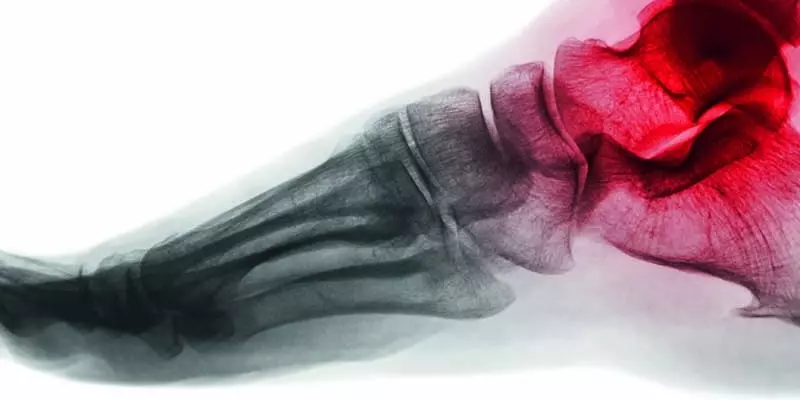

Fizjoterapia jest dziedziną medycyny, która może stanowić wartościowe uzupełnienie dla innych dziedzin medycznych. Większości efektów jej leczenia nie można uzyskać farmakoterapią czy nawet chirurgią. Fizykoterapia, masaż czy kinezyterapia okazują się przydatne w wielu czasem bardzo zaskakujących specjalnościach medycznych. Jedną z nich jest medycyna estetyczna.

Ma ona swoją specyfikę. Nieco odrębne są cele i stosowane procedury. W ślad za tym inne są kwalifikacje do zabiegów, sposób ich przeprowadzania oraz nieco odrębne postępowanie pozabiegowe. Nie zmienia to jednak faktu, że są to zabiegi medyczne i wszystkie etyczne uwarunkowania z nimi związane są w pełni obowiązujące. Zdrowie pacjenta oraz jego bezpieczeństwo powinno być stawiane na pierwszym miejscu.